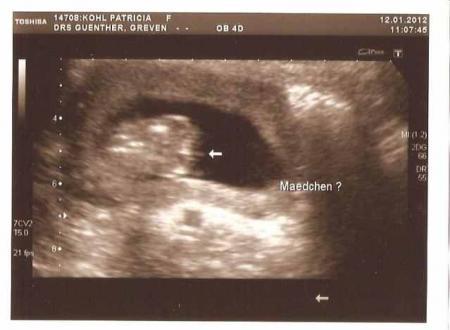

Dankeschön an alle neuer versuch mit dem Bild

Bild zu

dann halt über tinypic. ich glaub bei RUB stimmt was nicht http://i41.tinypic.com/inby8i.jpg